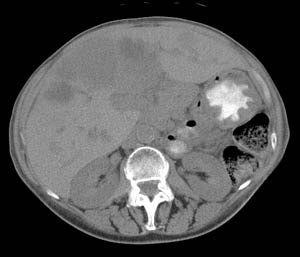

VIPoma: The patient shown below presented for evaluation of a 9 month history of intractable diarrhea and an elevated VIP level. Previous conventional imaging studies had been negative. The In-111 Octreotide study demonstrated a large area of intense uptake within the pancreatic tail (black arrow on transaxial SPECT images). Repeat CT imaging confirmed the presence of a VIPoma within the pancreatic tail (white arrows). |

|